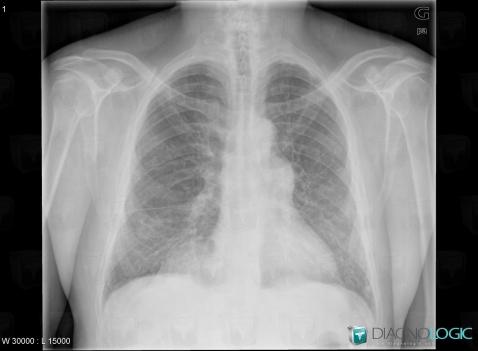

COPD, Pulmonary parenchyma, X rays

Here is the specific information in the key image above:

- Diagnosis COPD, Location(s) Pulmonary parenchyma, with gamuts